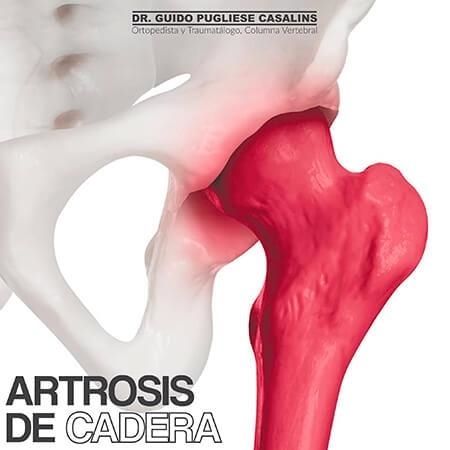

Las especialidades de Dr. Guido Pugliese Casalins son: Ortopedista y traumatólogo, Ortopedista de columna vertebral, Escoliosis.

Presentaba una escoliosis desde niña que se me fue aumentando, apesar de que yo seguia todas las indicaciones de los medicos que me veian, progreso tanto que me daba pena usar ropa ajustada o vestido de baño. Otros medicos me decian que una cirugia era muy peligrosa porque podia quedar en silla re ruedas, y me recomendaron al Dr Guido una persona que habia operado de lo mismo, me anime y me someti a la cirugia. Desde ese dia mi vida cambio, me recupere rapidamente, hoy hago todas mis actividades normles y no me da pena ni usar vestido de baño. Gracias Dr Guido por cambiarme la vida !!!